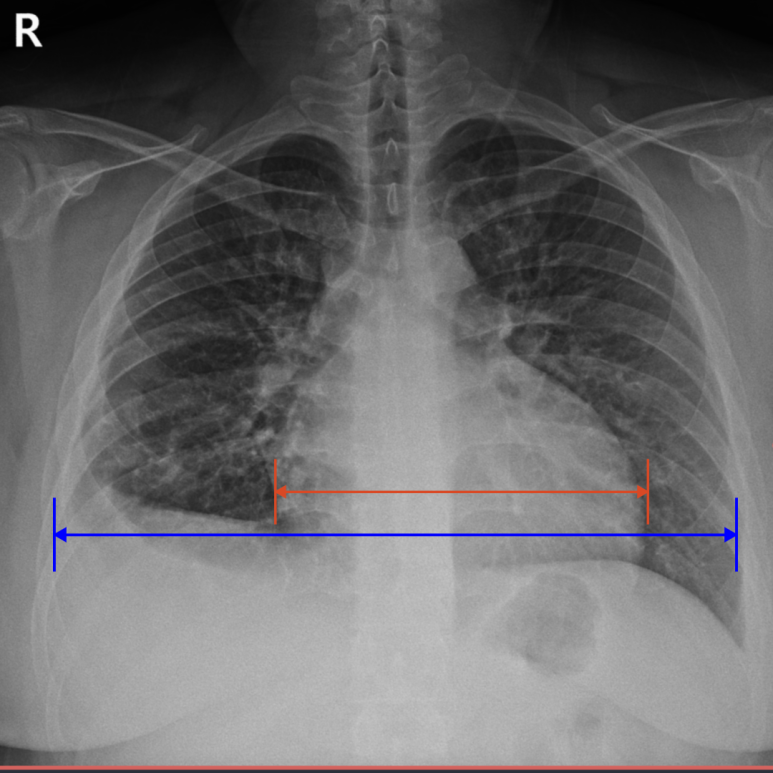

1. X-RAY

• X-RAY 검사에 확인된 심장비대 X-RAY 검사에 확인된 심장비대